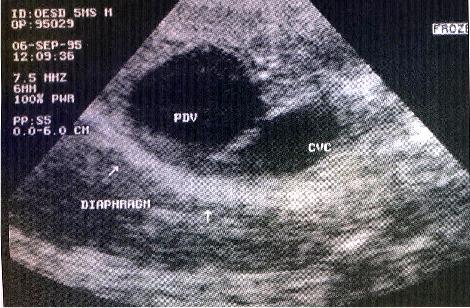

Ultrasound image of the liver from a dog with a portosystemic shunt.

Note large anomalous patent ductus venous (PDV) adjacent to the caudal vena cava (CVC)